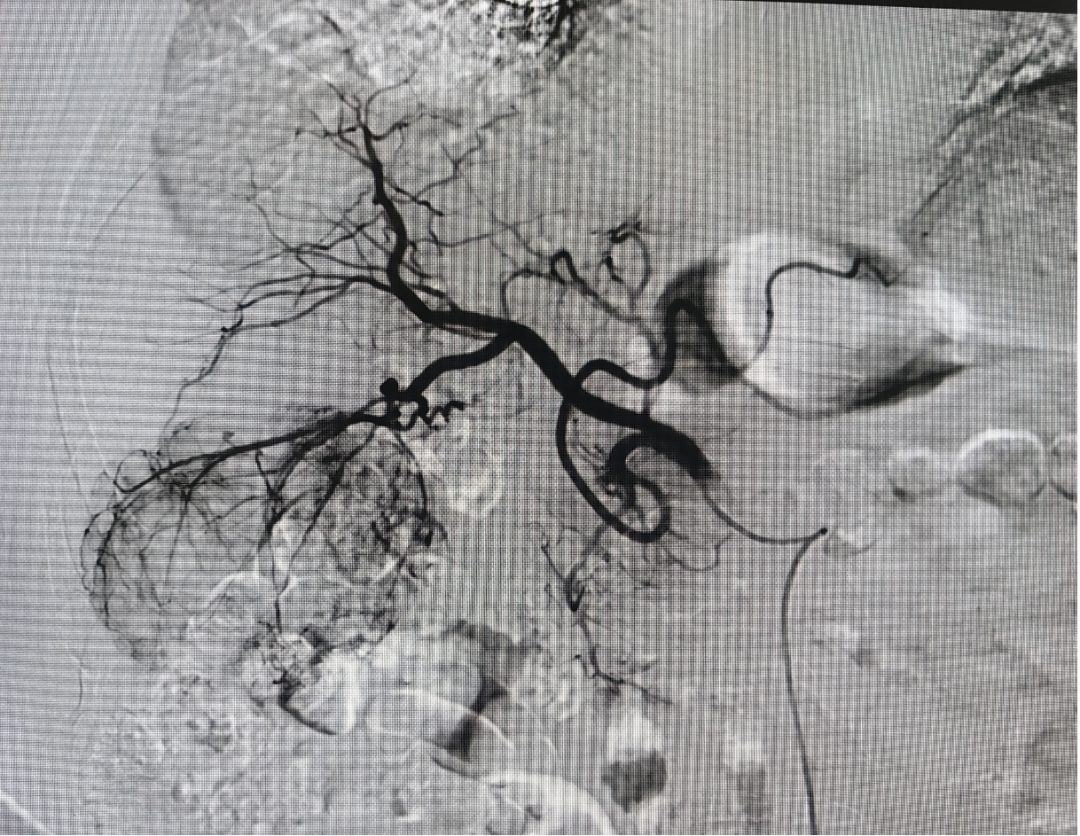

案例1 :61岁,肝癌术后、碳离子治疗复发,腹部MR示:肝左叶占位性病变治疗后复查,大小约 4.3x4.8 cm(S2501,I19),较前病灶范围略增大,边缘欠光并强化明显,邻近肝内胆管扩张及门静脉左栓子形成新出;肝左叶包膜下异常强化结节,较前新出,转移可能。采用载药微球介入治疗后,病灶完全坏死。

案例2 :68岁原发性肝癌患者(肿瘤8cm),通过DEB-TACE治疗,肿瘤血供完全阻断,肝功能稳定,为后续转化手术创造机会。

术前 术后